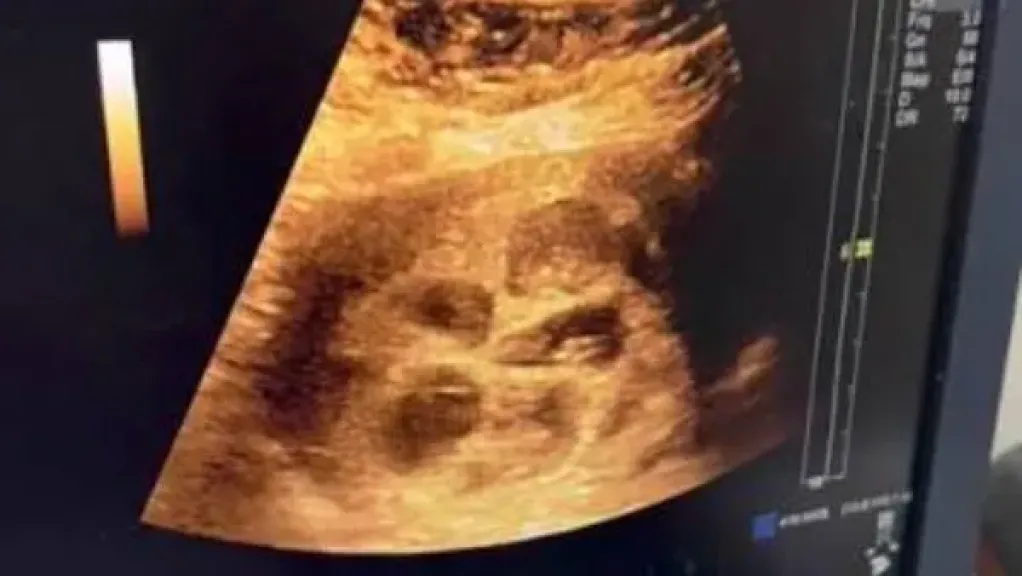

في حادثة طبية غير مألوفة، شهدت محافظة قنا ولادة سيدة لثمانية توائم دفعة واحدة، وذلك بعد رحلة طويلة من المعاناة مع تأخر الإنجاب لمدة 4 سنوات.

الدكتور عمرو أبو العباس، استشاري النساء والتوليد، أوضح عبر صفحاته الرسمية أن هذا الحمل حدث بشكل طبيعي تمامًا، دون اللجوء إلى أي نوع من وسائل الإخصاب المساعد كأدوية تنشيط التبويض أو الحقن المجهري.

وكشف الدكتور أن الزوجة كانت تعاني من بعض المشكلات الصحية، منها تكيسات على المبايض واضطرابات هرمونية، إلى جانب تأخر الإنجاب.

ومع ذلك، تمكن الزوجان من تحقيق هذا الإنجاز الطبي بعد اتباع برنامج علاجي مكثف ومتابعة طبية دقيقة.

أشار الطبيب إلى أن هذه الحالة قد تكون مؤهلة للدخول في موسوعة جينيس للأرقام القياسية باعتبارها واحدة من الحالات الطبية النادرة حول العالم.

وعبر عن دهشته من أن الحمل حدث بشكل تلقائي ودون أي تدخل طبي في التخصيب.